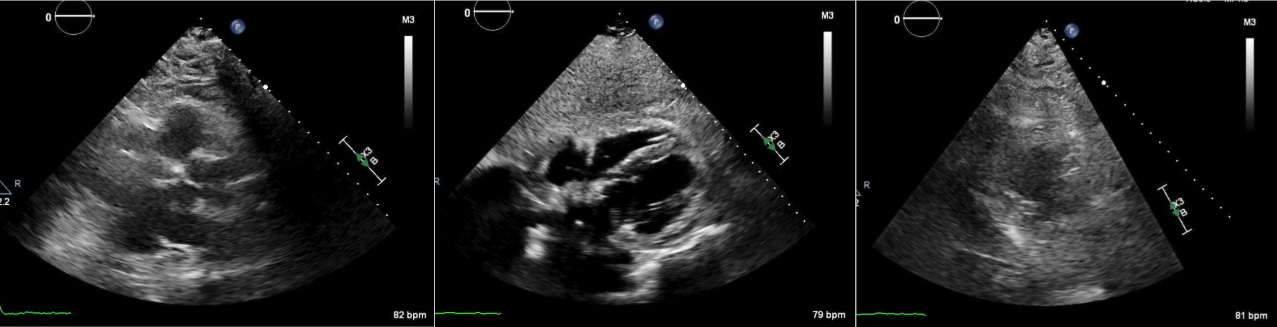

Abstract Body (Do not enter title and authors here): Case Description: A 71-year-old male presented to the hospital for dyspnea and chest discomfort for the past 2 weeks. He has a history of AAA status post stent and current tobacco use with emphysema. On admission, he was found to be tachycardic with rates reaching as high as 180 with systolic blood pressure of 89/61 and hypoxic with SpO2 of 80%. EKG revealed AFib with RVR with no acute ischemic changes. Troponins were negative and proBNP was 307. Infectious workup was negative. CTA chest showed no evidence of PE or dissection, however, moderate pericardial and bilateral pleural effusion was shown with mediastinal lymphadenopathy. After starting an esmolol and amiodarone drip, he converted to sinus tachycardia. TTE showed an EF 55%, echo dense debris measuring 2 cm with 1 cm effusion within the pericardial space resulting in significant compression of RA and RV. Findings were concerning for tamponade evidenced by invagination of RA and RV during systole and diastole respectively and greater than 50% variation and tricuspid inflow velocities with respiration. He was taken emergently to the OR for a pericardial window, thoracentesis, and chest tube. 300 mL and 400 mL of cloudy straw-colored fluid were removed from the pericardial and pleural space respectively. Fluid studies were negative for malignant cells and cultures remained negative. Repeat TTE showed an EF 55%, with epicardial fat pad and small posterior pericardial effusion. ANA testing was positive; however, other autoimmune studies are negative. His symptoms improved and he was discharged home.

Discussion: Cardiac tamponade is commonly caused by large pericardial effusions. Mild pericardial effusion less than 1 cm on TTE does not typically cause symptoms. However, the presence of significant pericardial debris can be problematic with minimal pericardial effusion. In this case, the patient developed cardiac tamponade complicated by AFib with RVR. Fortunately, hemodynamics and symptoms improved post pericardial window draining 300 mL of bloody fluid, but the diagnosis remains unknown given negative fluid studies. It's postulated that the debris is inflammatory in nature, but the absence of a diagnosis puts the patient at high risk for shock if the pericardial window fails. Patients with pericardial debris up to 2 cm on TTE with risk of developing pericardial effusion should be monitored with follow up TTE. Further studies are necessary to unveil the underlying etiology of large pericardial debris.